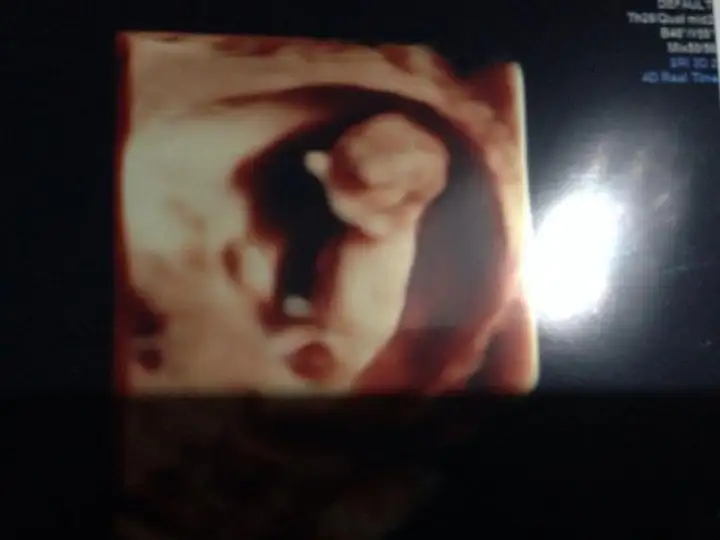

kiz cnm bnm ole gorunuo nub

Eki Görüntüle 1214628 %90 kız dedi bir hekim diğer başka hekim birşey söyleyemedi

Kiz canım öyle gozukuyorKIZLAR SİZCE BENİMKİ NE